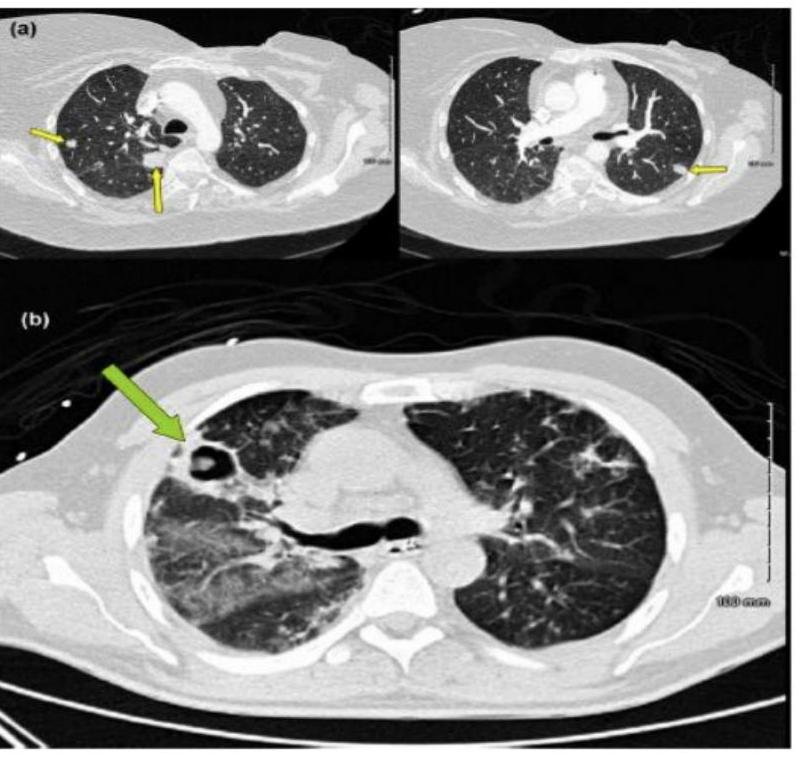

# ASPERGILOSIS ## DEFINICIÓN La Aspergilosis Invasora es la enfermedad causada por diferentes especies del **HONGO** género *Aspergillus*, a partir de un sitio de inoculación e **infección primaria**. El proceso de enfermedad incluye **angioinvasión**, **trombosis** y **tromboembolismo**; esto último, favorece la **diseminación** a otros órganos. La enfermedad invasora por *Aspergillus* afecta principalmente a pacientes **inmunocomprometidos** tales como: con **leucemia**, **linfoma**, **neutropenia prolongada**, **trasplantados** especialmente de **MO** y **pulmón**, aquellos tratados con **inmunomoduladores**, **inmunodeficiencias primarias**, con **enfermedad injerto contra huésped**, **anemia aplásica** y con terapia crónica con **corticosteroides sistémicos**. La forma invasora **incluye** las **infecciones** de las vías **respiratorias inferiores**, **senos paranasales** y **piel** como sitio de entrada. La **diseminación hematógena** o por contigüidad puede condicionar infección a nivel del **sistema nervioso central (SNC)**, cardiovascular y a otros órganos y sistemas. ## EPIDEMIOLOGÍA ## Aspergilosis Invasora: Típica aparición en **Leucemia Mieloide Aguda** y **Trasplantados**. - **Inmunocompromiso** - Mediana de edad 9-11 años (coincide con el pico de **incidencia de leucemias**) - **Neoplasias hematológicas** - **Neutropenia** < 100 cl/mm³ La presencia de **CAVITACIONES PULMONARES PREEXISTENTES** secundarias a infecciones por **Tuberculosis** facilita el desarrollo de Aspergilosis. ## Aspergilosis Broncopulmonar alérgica: - **Hipersensibilidad** asociada a **asma** - **Fibrosis quística** # CLÍNICA Es **inespecífica** en todas sus variables, por lo que es recomendable establecer la certeza diagnóstica con base en los **factores del hospedero** y sus **manifestaciones**. ## RIESGO INTERMEDIO Y ALTO - **Fiebre** y **dolor facial** - Las **lesiones isquémicas** y **úlceras** traducen un **diagnóstico tardío** Otras presentaciones: **Absceso cerebral**, **vasculitis**, **meningoencefalitis**. ## INFECCIÓN DISEMINADA ## ASPERGILOSIS CEREBRAL **Imágenes en anillo**. La aspergilosis **cerebral aislada** puede ocurrir en pacientes **inmunocompetentes**. **Signos neurológicos focales**, **alteraciones en el estado mental** y **cefalea**.  ## Enfermedad cutánea **Diseminación hematógena** o **infección local** (**inserción de catéteres**). **Quemaduras** y **heridas quirúrgicas**. **Eritema** de rápido crecimiento, con **centro necrótico**, frecuentemente **ulcerado**.  ## Aspergiloma * Una **esfera fúngica** coloniza **cavidad pulmonar preexistente** (**habitualmente una caverna tuberculosa residual**). * Se visualiza como **estructura redondeada** dentro de **cavidad pulmonar**, cambia de posición con los movimientos. * **Tuberculosis** 21 %, **no micobacterias** 20 %. ## Osteomielitis **Poco común**. **Extensión local** de **proceso pulmonar**, **sinusal**, **cerebral**. 1.ª en **enfermedad granulomatosa crónica** y **usuarios de drogas**.  # DIAGNÓSTICO ## GOLD STANDARD: CULTIVO / HISTOPATOLOGÍA / PCR / GALACTOMANANO ## CULTIVO Se debe identificar el nivel de la especie para la **susceptibilidad** de los **antimicóticos** disponibles **in vitro**. **Diagnóstico definitivo**. ## HISTOPATOLÓGICO Examen con **tinciones especiales**: PAS y/o Grocott Gomori. **Diagnóstico Definitivo**. ## GALACTOMANANO **Componente** de la **pared fúngica** excretado en la fase de **crecimiento del hongo**, siendo su nivel **proporcional a la carga fúngica** en el tejido. **Positivo en fusariosis**. **Diagnóstico Definitivo**. * Se mide en **suero** y en **lavado broncoalveolar**. * Puede haber **falsos positivos** con el uso de **pipetazo** y otros **betalactámicos**. ## RADIOGRAFÍA DE TÓRAX Se observan **cavitaciones** o **infiltrados**.  (c) Copyright 2021-2022 Joyas ENARM - Todos los derechos reservados - # TOMOGRAFÍA DE TÓRAX Debe realizarse de manera **inicial**, seguida de una **TAC de Alta Resolución** (**cortes finos de 1 mm**) si en la primera se identifica **anormalidad**. **SIGNO DEL HALO**: área de **opacidad en vidrio deslustrado** alrededor de un **nódulo** o **consolidación focal**. Se observa durante la **neutropenia** y es muy **característica** de la **infección invasora por hongos del pulmón**. **Presente** en el **60% de los casos** por 5-7 días posteriores a la **neutropenia grave**. ## TRATAMIENTO  ## **1.ª elección: VORICONAZOL** **Alternativas**: **Isavuconazol** **Efectos secundarios**: **alteraciones visuales**, **hepatotoxicidad** y **fotosensibilidad**. **FORMA INVASIVA**: **Anidulafungina**, **Caspofungina**, **Micafungina**.